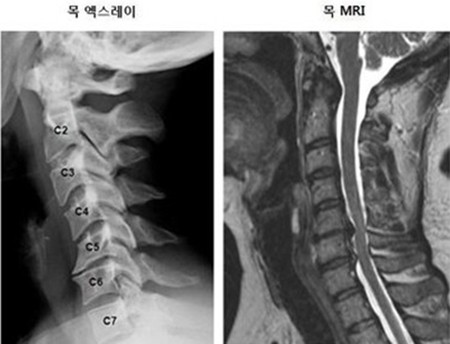

목 디스크는 목의 디스크(경추 디스크)에서 출현하는 질환으로, 경추 디스크 사이의 연골판이 터져 디스크 내부 물질이 경추 신경을 자극해 통증이나 저림증 등의 증상을 유발 해요. 목 디스크는 일상생활에서의 안 좋은 자세나 많은 운동, 부상 등이 이유가 되는 것이 될 수 있기도하고, 시간이 지날수록 발생 확률이 높아져요. 목 디스크의 증상으로는 목 부위의 통증, 팔의 저림, 근육 약화 등이 있으며, 증상이 난폭한 경우 수술 등의 치료가 필요할 수 있어요. 그리하나 대개의 경우 치료 없이도 시간이 지나면 증상이 호전되는 경우가 대부분입니다.

목디스크 증상 2. 목 자세

목디스크 증상 목 자세이고요. 현대인들은 스마트폰이나 모니터를 많이 사용하다보니 목이 앞쪽으로 당겨져있는 것처럼 자세를 많이 취하게 된다 하였습니다. 이런 자세는 정상적인 목뼈를 전환 시켜 여러분이 아시는 거묵목 증상이 나타나게 되는 이유가 되는 것입니다.